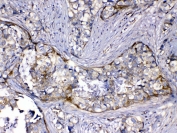

IHC testing of FFPE human intestinal cancer tissue with HOMER3 antibody at 1ug/ml. Required HIER: steam section in pH6 citrate buffer for 20 min and allow to cool prior to testing.